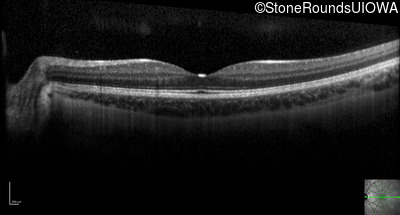

Optical Coherence Tomography - Right - 20/16 -1

Exemplar / OCT Stack